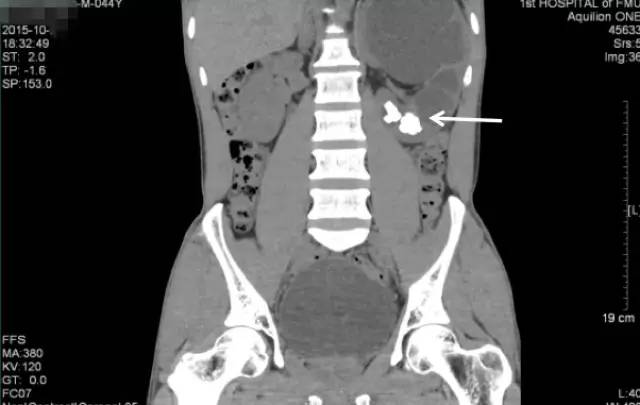

入院后进一步行泌尿系CT平扫+三维重建

CT三维重建图像可见左肾明显增大、扩张积水、多发结石